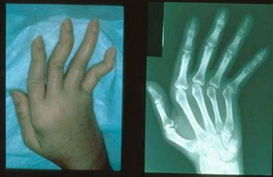

关节痛不仅仅是风湿性关节炎早期症状,也是类风湿性关节炎、强直性脊柱炎等疾病的早期症状。各类疾病的疼痛多区别于不同部位。风湿性关节炎早期症状的关节红、关节肿、关节热、关节痛,常常是膝、髋、踝等下肢大关节,其次是肩、肘。一般不会是手指、腕等小关节。推荐阅读:引起发生风湿性关节炎的原因